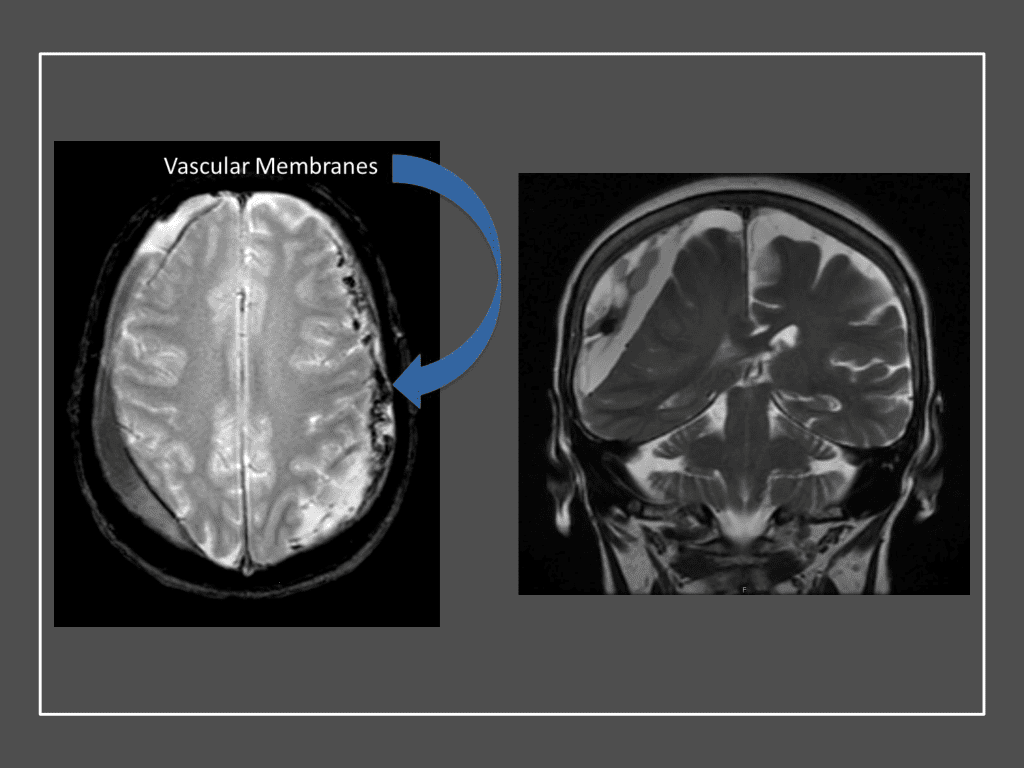

A woman in her 80s developed mild dizziness and headache following incidental trauma working in her garage one day. She presented several weeks later to the ER and was diagnosed with bilateral subdural hematomas, which were initially managed with observation, low dose Decadron, considering the mildness of symptoms, advanced age, and history of CLL with thrombocyptopenia (<100k). Over the next 4 weeks, the collections remained relatively stable with evidence of slight growth (10 to 12 mm thickness, and 2 mm right to left shift) on NCT (Figure 1. A and B).

Figure 1. A) 6 weeks post mild trauma B) 4 weeks post mild trauma demonstrates stable subacute subdural collections with mild growth and sulcal effacement.

CT follow-up at 1 week demonstrates early resorption. 2 weeks post MMA embolization, resolution of the left subdural collection with new small thin acute hemorrhage in an otherwise stable right subdural collection is observed (Figure 3. A and B).

Figure 3. A) 1 week post MMA embolization demonstrating decreasing thickness bilaterally B) 2 weeks post MMA demonstrates resolution on left, with small new acute component on right with overall decreased thickness.

Clinically, the patient improved over the few weeks with the occasional transient twinge of a headache, but resolution of dizziness. Follow-up CT at 10 weeks demonstrated complete resolution of the bilateral subdural hematomas with our patient completely asymptomatic and back to all of her activities of daily living. Considering her history of thrombocytopenia and CLL, we will continue to monitor her into the future and are excited about her progress and recovery. (Figure 4. A and B)

Figure 4. A and B) – 10 weeks following embolization demonstrates complete resolution of bilateral collections both acute and chronic.